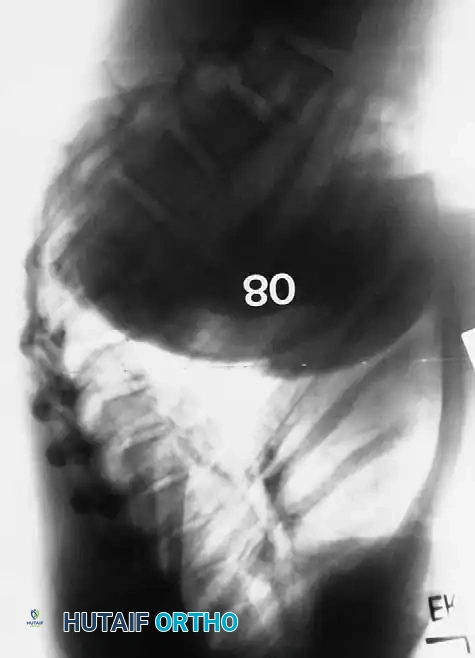

Preoperative lateral radiograph highlighting the rigid structural curve.

A lateral radiograph taken with the patient hyperextended over a bolster is critical to assess the flexibility of the curve and to aid in preoperative planning.

Postoperative Radiographic Outcomes

Postoperative lateral radiograph showing excellent restoration of thoracic kyphosis and sagittal balance.

Postoperative lateral radiograph demonstrating correction of a severe thoracolumbar curve.

Long-term follow-up lateral radiograph showing solid arthrodesis and maintenance of correction.